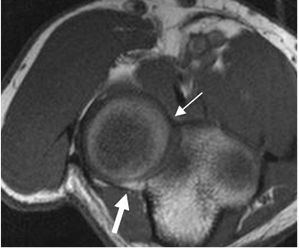

Los nervios se identifican como estructuras redondeadas y mejor vistos en cortes axiales. (4). Normalmente están rodeados por líquido y tienen señal intermedia en T1 y elevada en T2, en relación con el músculo. (10).

El nervio ulnar cruza por el túnel de su nombre, por detrás del epicóndilo medial y está fijado por el ligamento arcuado. Hasta en el 15% de la población, el nervio puede estar sub o dislocado, por ausencia del ligamento, como variante normal. Esta variante predispone a neuritis, aunque la mayoría de individuos son asintomáticos. (4). (Fig 22 y 23).